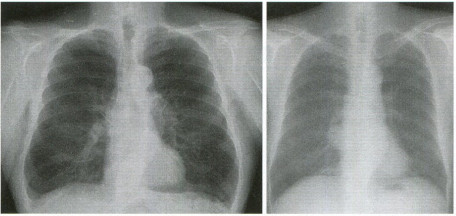

초음파에서는 왼쪽 갈비뼈 한 곳에 미세 골절이 확인됐고 갈비뼈 형성이 진행된 상태에서 골절은 1~2주 전에 발생했을 가능성이 높았습니다. 갈비뼈 골절 진단 후 환자는 통증에 대한 약물 치료 및 윤동 제한 및 안정 후 증상 호전 및 골절 부위 유착으로 회복되었습니다.

▶ 치료 통증 조절 운동 제한 및 안정 : 처음 3~4주 동안은 격렬한 활동을 피해야 하며, 적어도 6주 동안은 운동을 피하는 것이 좋습니다. 다음으로 아프지 않은 범위 내에서 육체적인 활동을 시작할 수 있습니다.